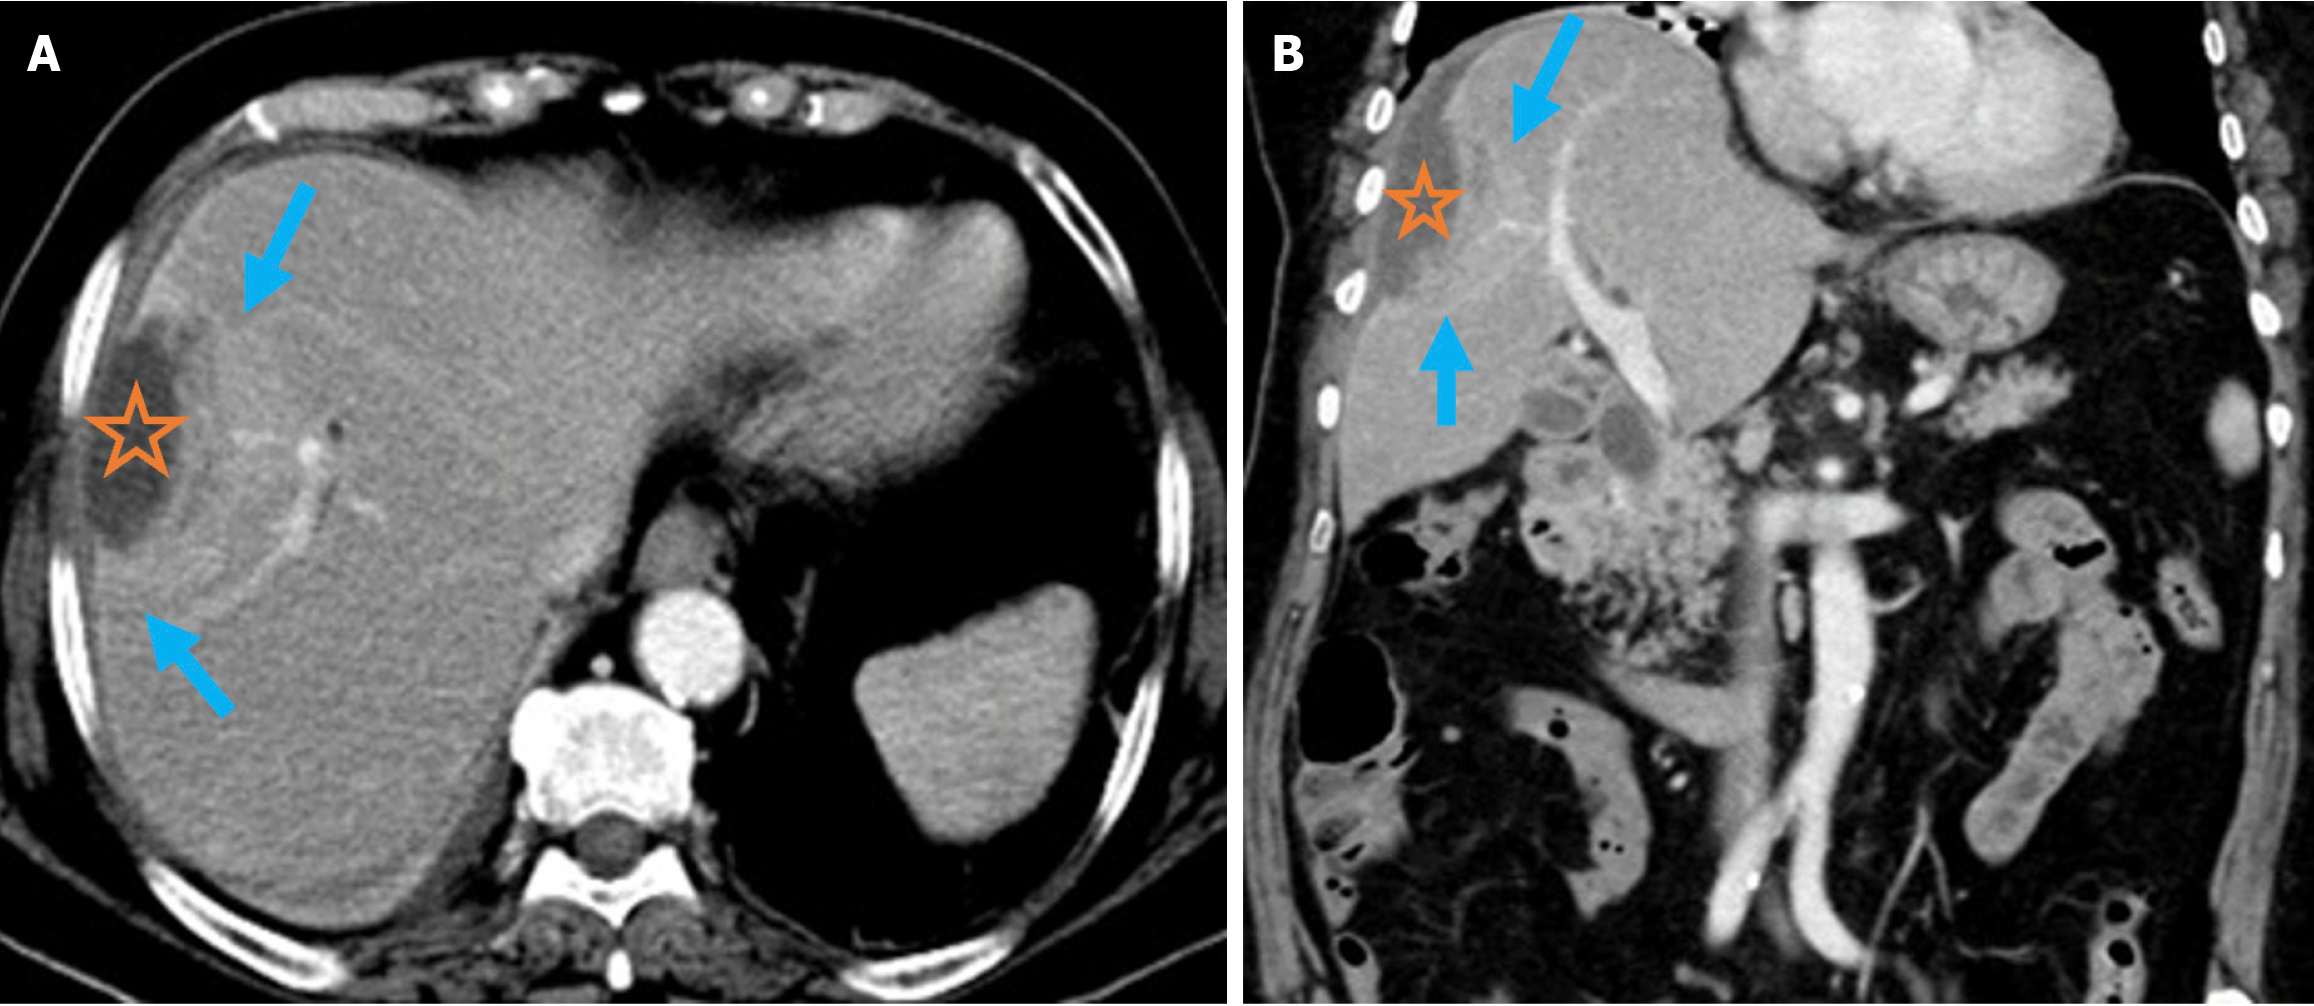

A hepatic abscess appears as a heterogeneous solid mass on CT in the early stages. It typically develops a peripheral contrast-enhancing rim with a centrally hypoattenuating core as it progresses. Pyogenic liver abscesses may be difficult to differentiate from necrotic tumors. The double target sign in which the outer wall layer enhances later than the inner wall layer is an important feature for differentiation. Abscesses usually appear hypointense on T1-weighted MRI and hyperintense on T2-weighted MRI. Peripheral rim enhancement shows the double target sign on contrast-enhanced sequences and typically yields low apparent diffusion coefficient values on diffusion-weighted imaging (Figure 8)[5355].

Figure 8

Figure 8 Pyogenic liver abscess. A and B: Axial (A) and coronal (B) contrast-enhanced computed tomography images demonstrated pyogenic liver abscess secondary to endoscopic retrograde cholangiopancreatography in a 76-year-old female patient. She presented 2 months after endoscopic retrograde cholangiopancreatography with abdominal pain, nausea, elevated acute phase reactants, and leukocytosis. A hypodense lesion corresponding to the abscess was apparent in the right hepatic lobe (orange star). Surrounding edema and increased perfusion were also noted. This imaging appearance represents the double target sign (blue arrows).